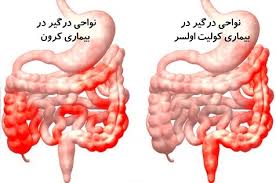

قیمت: 49٬000 تومان - دسته بندی فایل: پاورپوینتپاورپوینت کولیت اولسروز و کرون (ppt) 35 اسلاید

فروش ویژه پاورپوینت حرفه ای کولیت اولسروز و کرون / تعداد اسلاید : 35 اسلاید